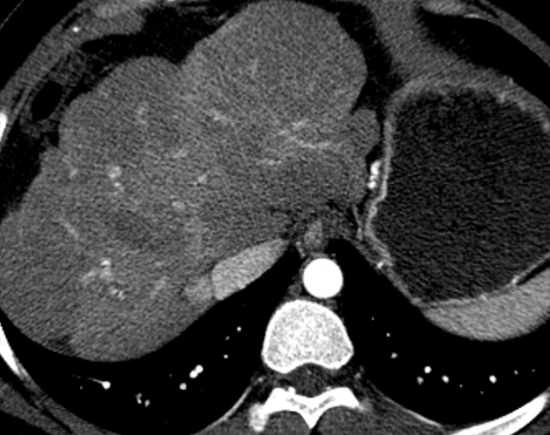

간 결절이란 간 조직 내에서 국소적으로 형성되는 작은 혹 형태 구조물을 말합니다. 주로 초음파, CT, MRI 검사에서 우연히 발견되는 경우가 많으며, 대부분은 양성 변화로 평가됩니다. 하지만 ‘간 결절 치료방법’을 고민하게 되는 이유는, 일부 경우 결절이 커지거나 악성 가능성이 있는 병변으로 의심되기 때문이죠.

간 결절의 종류에는 간 혈관종, 간낭종, 지방간 관련 혹, 간세포성 병변 등이 있습니다. 각 종류마다 환자 개개인의 상태에 따라 관리 방식이 달라질 수 있습니다. 예를 들어, 제가 관찰한 사례에서 한 지인은 간 혈관종이 약간 커진 상태로 발견되었지만, 병원 진료 후 단순 양성으로 판단되어 바로 치료하기보다는 생활습관 변화와 정기 추적검사를 택했어요.